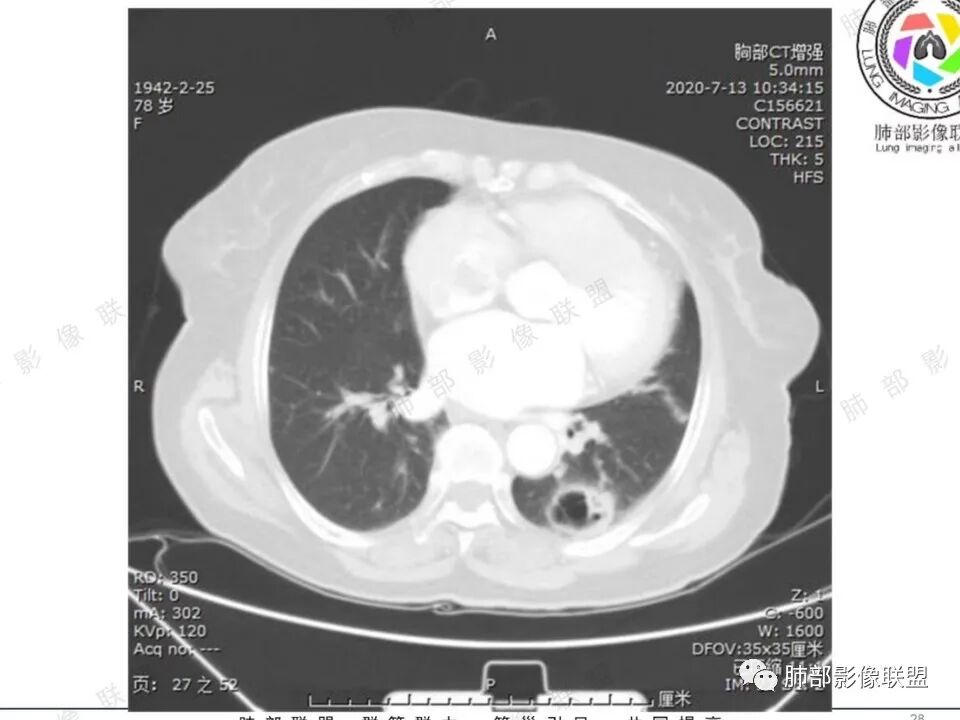

穿越七海的风: 右肺下叶不规则结节伴空洞,似鬼脸,壁厚度不均,壁内结节,首先考虑恶性,既往甲状腺癌病史,不除外转移。

蔡笑燕: 右肺不规则实性囊腔结节,囊腔内有血管走形和分隔,有分叶,细短毛刺,周围有清晰磨玻璃,胸膜牵拉,考虑IAC。

看图说话: 不规则结节,假大空,壁结节,边缘收缩,胸膜牵拉,周围有分叶,毛刺,伴有清晰磨玻璃影,周围有小结节,考虑肺腺癌,鉴别:1:结核,2,隐球菌。

哦落花时节 (刘朋): 中青年男性,右肺下叶不规则结节,内见多发囊腔,囊腔内壁不光滑,邻近叶间裂明显局部凹陷,有胸膜牵拉,血管聚集,考虑囊腔性腺癌,鉴别转移。

清茶: 青年男性,右肺下叶高密度结节影,有毛刺、分叶,内见空洞,边界尚清,考虑恶性,腺癌可能。

王秀仙: 右下肺 囊腔性结节,囊壁不均匀增厚,壁结节,毛刺分叶,胸膜凹陷,周边有边界清楚磨玻璃影,考虑囊腔型肺癌,腺癌。

心灵鸡汤: 青年男性,有甲状腺癌穿刺活检病史, 右肺下叶不规则囊腔,内壁不光整,似见壁结节,偏远侧见实性结节,病灶边缘可见分叶,毛刺,邻近血管支气管走行不自然,邻近斜裂牵拉,考虑二元,恶性结节,腺癌可能性大,转移、结核待排。